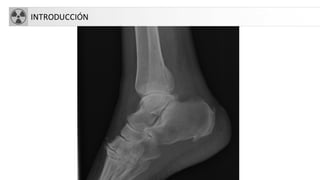

• Rx simple: primera exploración a realizar

• Antecedentesy valoración clínica: edad,

localización,síntomas, tiempo evolución…

• Aspectos técnicos:

– 2 proyecciones: AP y lateral (90º una de otra)

– Incluir 2 articulaciones adyacentes

– 2 miembros(imágenes comparativas)

– 2 exploraciones sucesivas para ver evolución